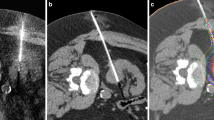

Percutaneous renal cryoablation procedure

A Siemens SOMATOM Definition AS CT system was used in the scanner suite alongside a BTG system (BTG, London, UK) for cryoablation. The procedure was performed by one of four radiologists with between 1 and 10 years of dedicated ablation experience. During the procedure, patients were in general anesthesia, and in a prone-oblique position.

For planning and target facilitation, a contrast-enhanced triple-phase CT scan of the kidneys was conducted. If needed, an intraprocedural coaxial biopsy of the tumor was performed using an 18-gauge semiautomatic needle prior to cryoprobe placement. Real-time CT fluoroscopy was used to guide needle placement. The number and type of cryoprobes were determined by the attending radiologist. If necessary, hydrodissection with sterile saline was carried out to displace thermally sensitive structures. At the discretion of the attending radiologist, truncated helical acquisitions covering the RM were acquired during placement of cryoprobes to confirm their position. In all cases truncated helical acquisitions for monitoring of the size and location of the ice ball were performed during two treatment cycles of freeze–thaw treatment (in general 10 min freeze, 8 min thaw, 10 min freeze) at 4-min intervals for a total of four acquisitions to confirm extension of the ice ball at least 5 mm beyond the tumor margin. The duration of each cycle and the power of each probe could be adjusted as to prevent adjacent vulnerable organ injury or inadequate ice ball coverage. Fluoroscopy was conducted as sequential scans at 5.0 mm slice thickness with 120 kV and a starting point of 40 mAs, which could be increased according to patient size. Images for the triple-phase CT were obtained as helical acquisitions at 2.0 mm slice thickness using standard CT technique (120 kV peak and approximately 200 mAs) with dose modulation using automatic exposure control. The same parameters were used in addition to a current of 150 mAs for the truncated CT acquisitions.